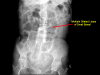

Case presentation: We report the case of an 82-year-old Caucasian woman presenting with a one-day history of generalized abdominal pain, with three episodes of vomiting. An abdominal X-ray displayed multiple dilated loops of the small bowel. A subsequent computed tomography scan of the abdomen and pelvis revealed a thickening of the duodenum and dilatation of the proximal jejunum. Multiple small bowel diverticula were identified with surrounding pockets of free air adjacent to the jejunal diverticula suggestive of a small bowel perforation. Our patient underwent a laparotomy, which identified multiple jejunal diverticula with two pinhole jejunal perforations and associated fecal contamination. The perforations were repaired with primary closure and extensive washout was performed.